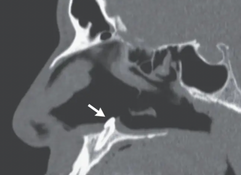

“Computed tomography of the paranasal sinuses showed a well-defined, radiodense mass consistent with an inverted ectopic tooth in the nasal cavity (Panel B, arrow), which was thought to explain the obstructive symptoms and septal perforation.

“On rhinoscopy, a hard, nontender, white mass was observed in the floor of the right nostril (Panel A).